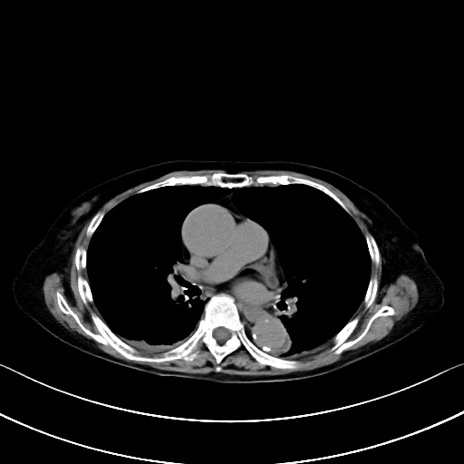

横断像